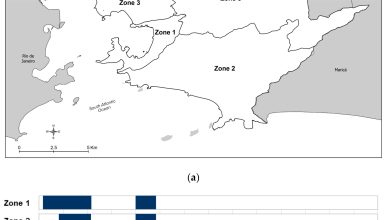

Em meio a uma epidemia global de dengue, um programa manteve uma cidade brasileira segura

Áreas e linha do tempo de liberação de Wolbachia em Niterói, Brasil. (a) Mapa de Niterói mostrando as zonas de…